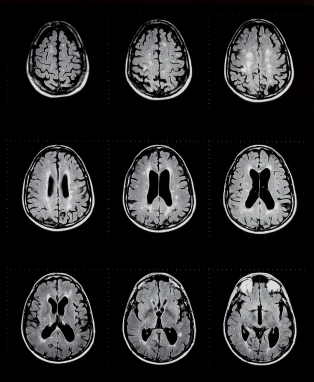

МРТ является магнитно-резонансная томография, специальный тест визуализации, которая не использует рентгеновских лучей. Эта процедура дает очень подробные изображения мозга, структуры лица, и пазух. В целом, МРТ лучше, чем КТ при определении острых приступов, инфекции и рак. Внутривенно краситель называется гадолиний иногда используется для получения лучшего изображения.